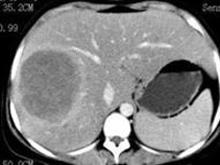

糖原累积病是一类由于先天性酶缺陷所造成的糖原代谢障碍疾病。根据欧洲资料,其发病率为 1/(2万~2.5万)。糖原合成和分解代谢中所必需的各种酶至少有 8种,由于这些酶缺陷所造成的临床疾病有12型,其中Ⅰ、Ⅲ、Ⅳ、Ⅵ、Ⅸ型以肝脏病变为主;Ⅱ、Ⅴ、Ⅶ型以肌肉组织受损为主。这类疾病有一个共同的生化特征,即是糖原贮存异常,绝大多数是糖原在肝脏、肌肉、肾脏等组织中贮积量增加。仅少数病种的糖原贮积量正常,而糖原的分子结构异常。